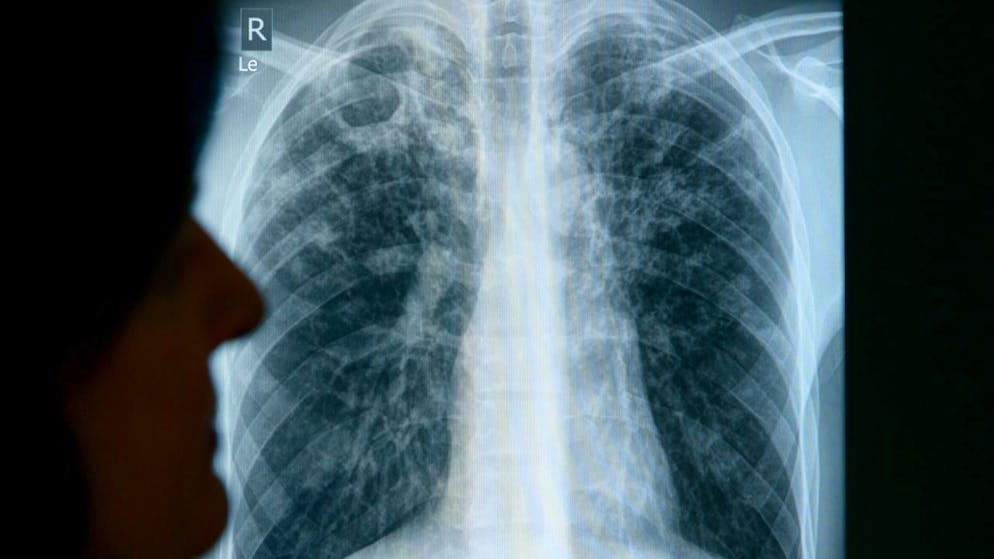

Sono in aumento i casi di tubercolosi in Svizzera

I casi di tubercolosi sono in aumento in Svizzera, in particolare a causa dell'arrivo di persone provenienti da regioni del mondo in cui la malattia è più diffusa, ha indicato l'Ufficio federale della sanità pubblica (UFSP) a Keystone-ATS.

Dall'inizio dell'anno sono stati segnalati 475 casi, contro i 376 e i 375 dello stesso periodo dei due anni passati, ciò che rappresenta un aumento del 26% per l'anno in corso. Va detto che l'incremento non riguarda le persone nate in Svizzera.

L'UFSP aveva già rilevato un aumento dei casi di tubercolosi nel 2023. Ad essere particolarmente colpiti sono i giovani immigrati. Tra la popolazione nata nella Confederazione, sono soprattutto gli anziani ad essere malati, ha osservato l'UFSP. Molti di loro hanno contratto la tubercolosi da giovani, quando era molto più diffusa in Svizzera.